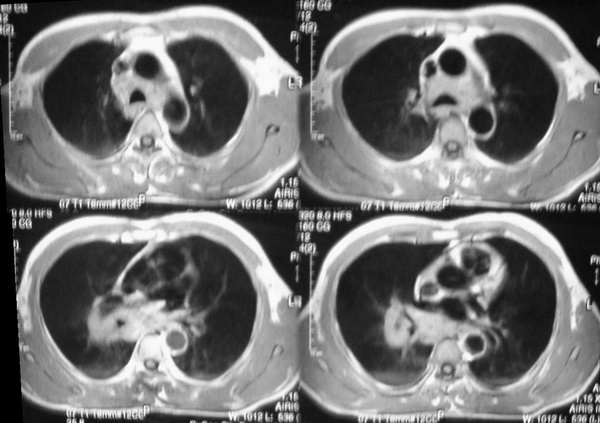

男,42岁。半年前体检发现右侧肺门肿大,mri示右侧肺门淋巴结肿大。腰背部疼痛伴右腿麻木1月入院。腹部b超示肝、胆、胰腺、脾、肾、前列腺及膀胱未见异常。afp、cea、ca199均正常。

胸部mri是半年前的,而胸部 增强ct是目前的,二者变化不大,肺部好像也没啥。

增强图像显示不清,好像有肺门及纵隔与腋下淋巴结肿大,右侧胸腔积液,腰1椎体骨质破坏,椎旁软组织肿块形成,其后硬脊膜囊明显受压。考虑淋巴瘤可能。其他待排。

胸部淋巴结肿大及腰椎改变,均考虑为转移性病变。